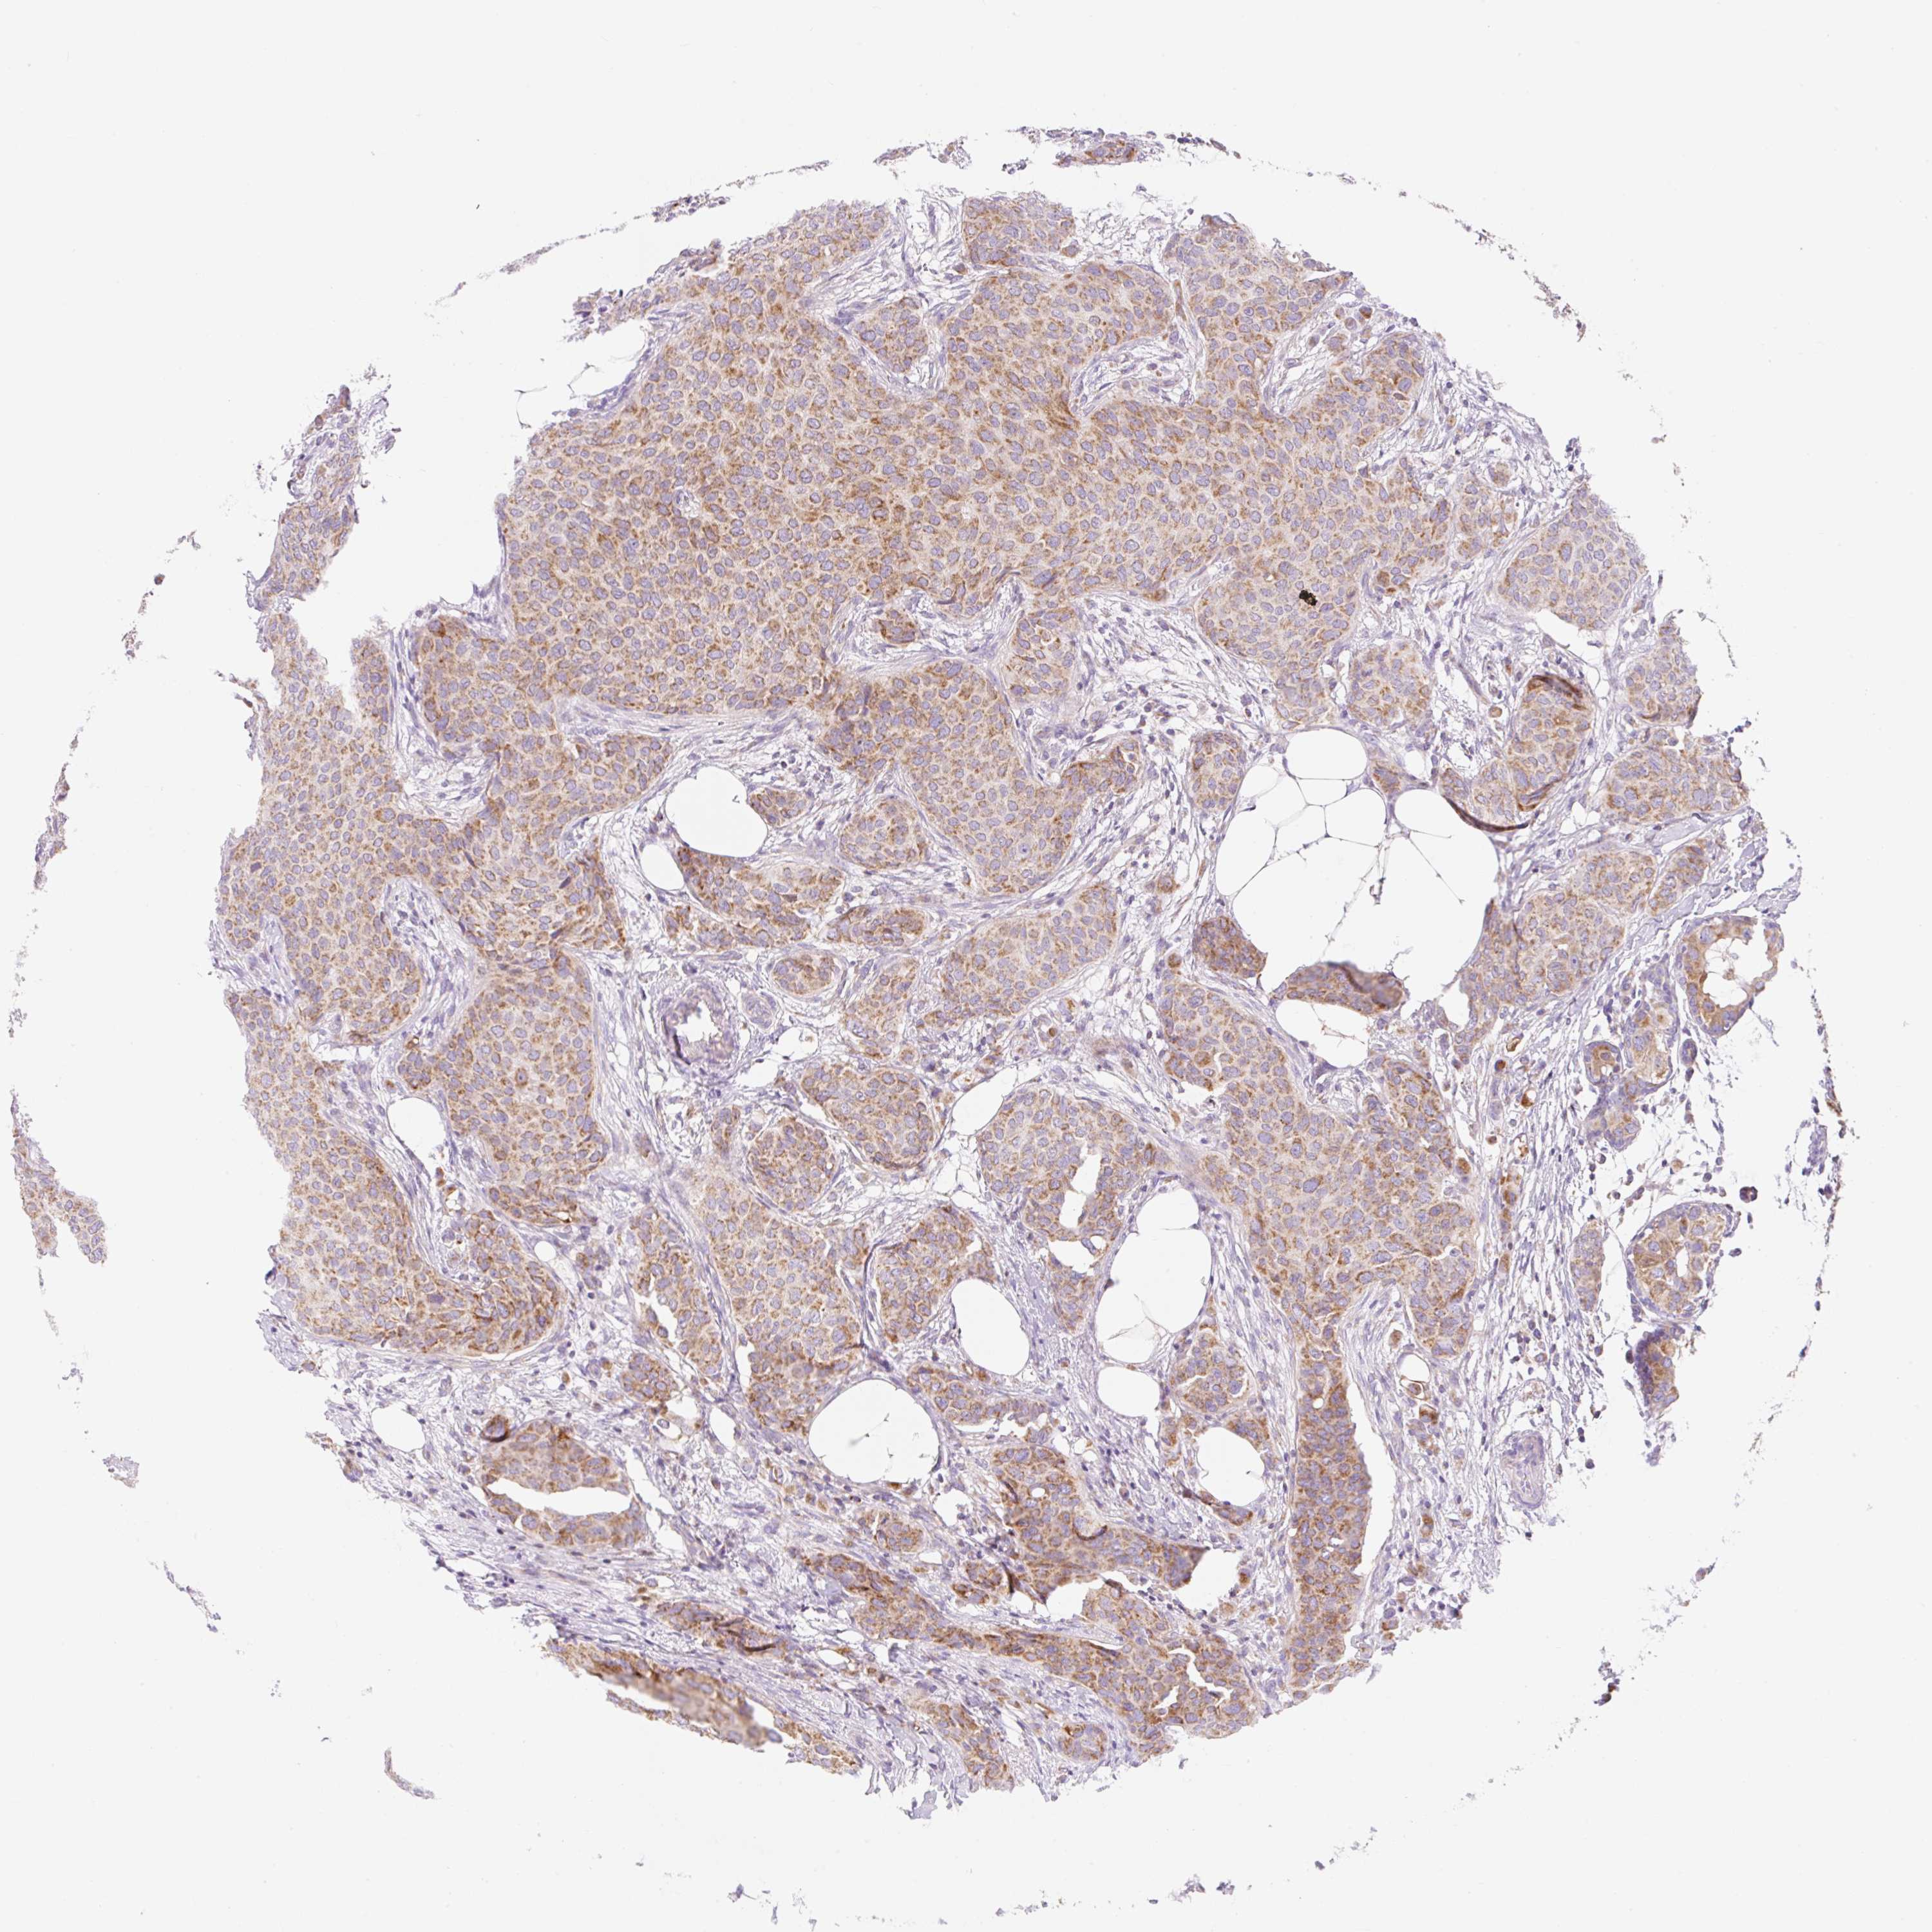

CANCER BREAST CANCER Show tissue menu

BRCA TCGA BRCA VALIDATION PROTEIN EXPRESSION